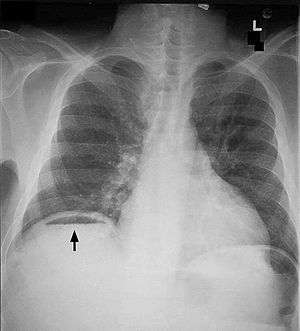

| Frontal chest X-ray. The air bubble below the right hemidiaphragm (on the left of the image) is a pneumoperitoneum. | |

Pneumoperitoneum is pneumatosis (abnormal presence of air or other gas) in the peritoneal cavity, a potential space within the abdominal cavity. When present, it can often be seen on radiography, but small amounts are often missed, and CT scan is nowadays regarded as a criterion standard in the assessment of a pneumoperitoneum.[1] CT can visualize quantities as small as 5 cm³ of air or gas. The most common cause is a perforated abdominal viscus, generally a perforated peptic ulcer, although any part of the bowel may perforate from a benign ulcer, tumor or abdominal trauma. A perforated appendix seldom causes a pneumoperitoneum.

Subphrenic abscess, bowel interposed between diaphragm and liver (Chilaiditi syndrome), and linear atelectasis at the base of the lungs can simulate free air under the diaphragm on a chest X-ray.